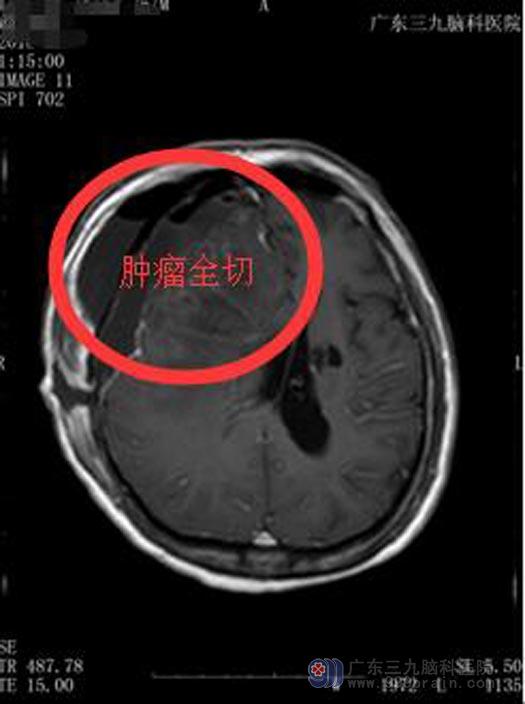

完善术前检查后,鲁明副院长主刀行“右侧额部占位病变切除术”,术中见肿瘤主体位于额部并侵犯脑膜,与周围边界模糊,肿瘤血供丰富,灰白色质软,显微镜下全部切除肿瘤、肿瘤周边受侵犯硬膜切除。术后病理:脑膜皮细胞型脑膜瘤,WHO I级。